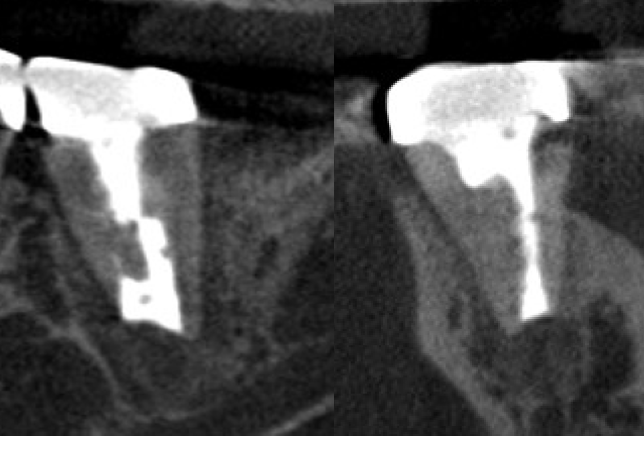

• 術前のCBCT画像、右上6の近心頬側根に透過像(炎症の黒い影)と未処置の根管MB2(赤色矢印)が見られ腫れている原因となっていることがわかる。

• 根管治療後一旦腫れが引いたものの、1ヶ月半で再発し歯根端切除術を行うこととなりました。術後のCBCTでは未処置だったMB2に根管充填がなされて殺菌できていることがわかります(緑矢印)。

• 歯根端切除前と術後半年のCBCT画像、感染源を除去してしっかり封鎖したことで、骨の再生を認め治癒が確認されました(黄色矢印)。